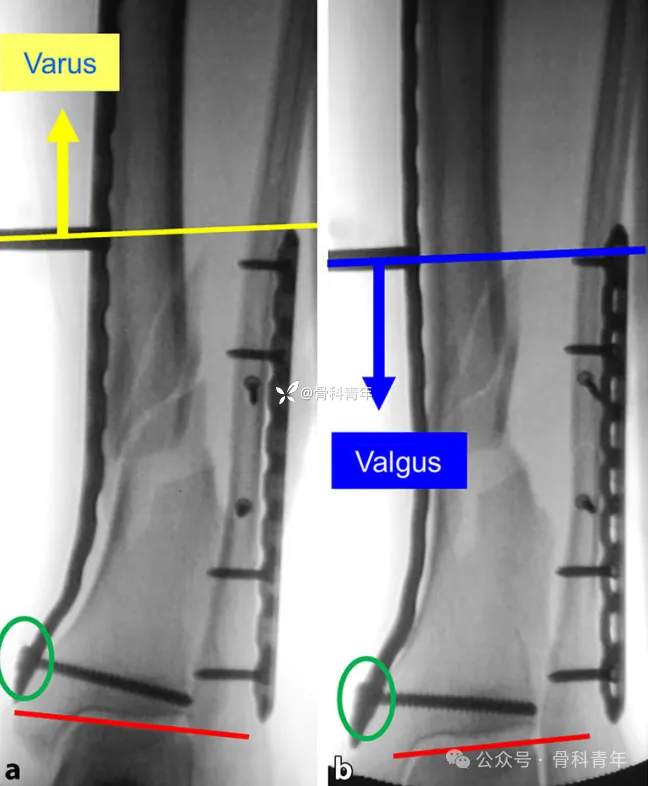

二、内翻/外翻畸形

明显的内外翻畸形通常合并腓骨/外踝骨折,对此类骨折,大多数医生选择优先固定简单骨折的外踝,恢复腓骨长度,作为胫骨复位的参考标准。胫骨内固定在内侧插入钢板后,先一枚螺钉固定远端,后在骨折线近端拧入锁定螺钉套筒,以套筒为操作杆上下移动,结合手法内外翻踝关节,以纠正内外翻畸形。

透视满意后,经上述锁定套筒置入螺钉即可。